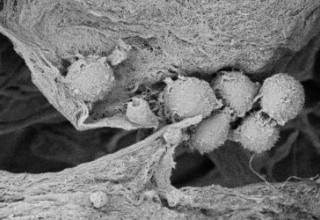

Cancer Stem Cells Embedded in Sanatela Matrix

When Sanatela researchers place a 6mm “disk-like” segment of the Matrix into a cell dish in the laboratory and then add patient leukemia cells, they immediately are drawn to, attach themselves and become embedded. Upon evaluation, these attached cells were found to have stem-cell properties. We believe other cancers will behave the same way. This process of seeding cell dishes with Matrix disks is clearly demonstrated in our video that can be found on the Sanatela website www.sanatelamedical.com